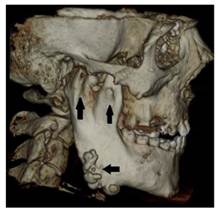

Figure 3

Osteomas at the left mandible angulus, mental protuberance and below the mandibular notch (white arrows)

Int J Med Sci Image

Figure 4

Osteomas at the right mandible angulus and also both condyle and coronoid process deformities (black arrow)

Dental volumetric tomographic (DVT) images showed multiple osteomas of the buccal cortex of the right mandibular angle and left mandibular angle (Figure 3,4). Additionally, in the coronal and sagittal sections of the mandible condyle, a huge osteoma that limited mouth opening was diagnosed (Figure 5). Cephalometrically, he showed a slightly retrusive maxilla with an ANB angle of 1˚and a relatively normal mandibula in anterioposterior direction. His mandibular plane angle (S-N / Go-Me: 25˚) and articular angle (S-Ar-Go: 133˚) were reduced (Table 1). His profile was straight due to the slightly retruded maxilla position. According to the Steiner's S line his lips were in normal position (Figure 6). The osteomas were submitted for pathologic examination. Histopathologic examination revealed that the specimens displayed a normal-appearing dense compact lamellar bone with minimal marrow spaces and rare irregular Haversian canals that did not show osteoclasts or osteoblasts (H&E X100)(Figure 7). Due to the dental anomalies, the osteomas in the mandible and the familial history of the patient, the patient was diagnosed as GS. Following resection of the osteomas that caused discomfort, prosthetic rehabilitation was performed.